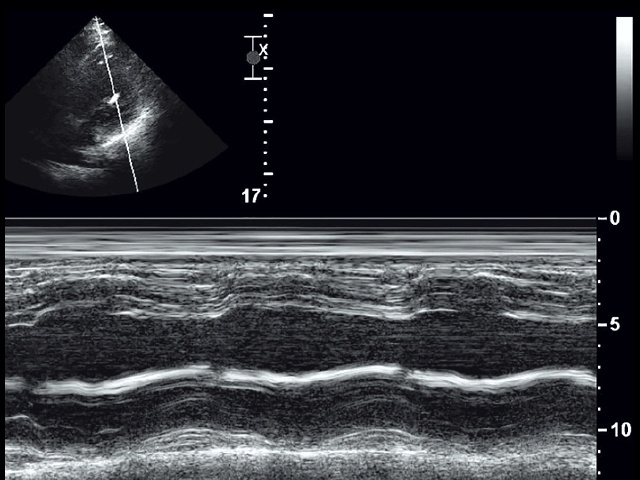

Эхографическая диагностика тромбов ЛЖ значительно проще, чем тромбов ЛП, чувствительность и специфичность ЭхоКГ достигают 90–95% [6, 7]. Для выявления тромба исследование проводится по длинной оси ЛЖ апикально в нескольких проекциях высокочастотным датчиком (5–7,5 МГц) максимальным разрешением в ближнем поле. Апикальное сканирование в нескольких плоскостях позволяет отличить тромб от трабекуляции или ложной хорды. Последняя выглядит как плотная линейная структура, прикрепляющаяся к пристеночной трабекуле. Тромб располагается в области гипо- и акинезии миокарда, в области верхушки ЛЖ придает ей не вогнутый, а выпуклый вид (см. рис. 1), эхогенность тромба обычно выше эхогенности миокарда, под тромбом нередко можно визуализировать тонкую эхопозитивную полоску эндокарда. Трансторакальная ЭхоКГ – метод выбора в диагностике тромбов ЛЖ. Трансэзофагеальная ЭхоКГ высокоспецифична (96%), но низкочувствительна (40–45%), так как при стандартном сканировании верхушка ЛЖ часто оказывается вне поля изображения, а удаленность от трансдьюсера затрудняет точную визуализа- цию структуры. Из дополнительных методов исследования следует указать на контрастирование полости ЛЖ, что существенно повышает качество диагностики в сомнительных случаях.